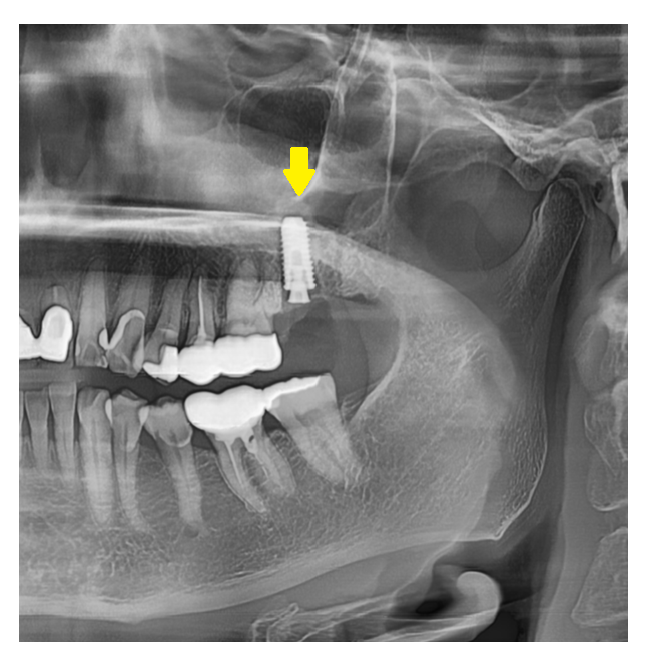

현재 구강 상태를 정확하게 파악하여야 하며

이때 잇몸 건강, 턱뼈의 양과 질 등

x-ray, 문진 등을 통하여 확인합니다.

턱뼈에 임플란트를 식립한 뒤

필요에 따라 골 이식을 진행하기도 하죠.

만약 잇몸뼈가 부족하다면 뼈이식을 먼저 진행하기도 합니다.

이후 임플란트가 턱뼈와 단단히 붙는

"골 유착" 기간을 기다립니다.

보통 3-6개월 정도 소요됩니다.

골 유착이 단단히 된 것이 확인되면